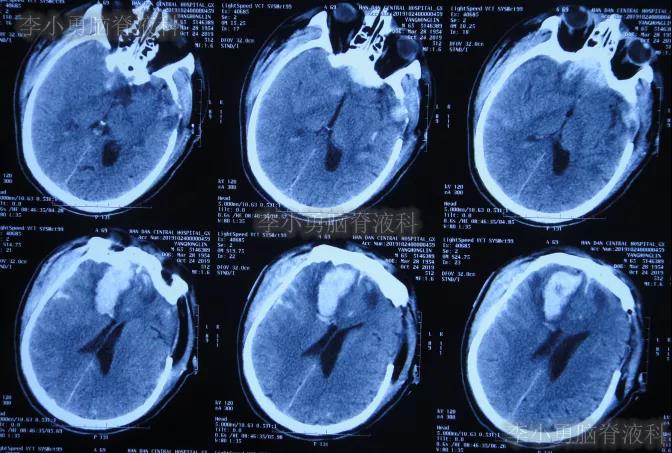

开颅术后18天即2019年11月7日,脑膨出进一步好转(图-9)。

图-9:2019年11月7日头颅CT

图-10:2019年11月15日头颅CT

开颅术后33天即2019年11月21日,查头颅CT(图-12)后认为无明显异常随后出院。

图-12:2019年11月21日头颅CT